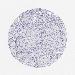

UROTHELIAL CANCER - Protein expressioni

A mouse-over function shows sample information and annotation data. Click on an image to view it in a full screen mode. Samples can be filtered based on level of antibody staining by selecting one or several of the following categories: high, medium, low and not detected. The assay and annotation is described here.

Note that samples used for immunohistochemistry by the Human Protein Atlas do not correspond to samples in the TCGA dataset.

Antibody stainingi

Antibody staining in the annotated cell types in the current human tissue is reported as not detected, low, medium, or high, based on conventional immunohistochemistry profiling in selected tissues. This score is based on the combination of the staining intensity and fraction of stained cells.

Each image is clickable and will lead to virtual microscopy that enables deeper exploration of all samples and also displays staining intensity scores, fraction scores and subcellular localization as well as patient and tissue information for each sample.

Antibody HPA006884

Antibody HPA006885

Antibody CAB002452

Urothelial carcinoma, Low grade

Urothelial carcinoma, High grade

Adenocarcinoma, NOS